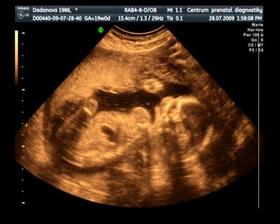

Naše maličké

Dne 15. 12. v 5:40 se nám narodil syn Jurášek. Vážil krásných 3500g a měřil ukázkových 50 cm. A je to nejkrásnější kluk na světě : )